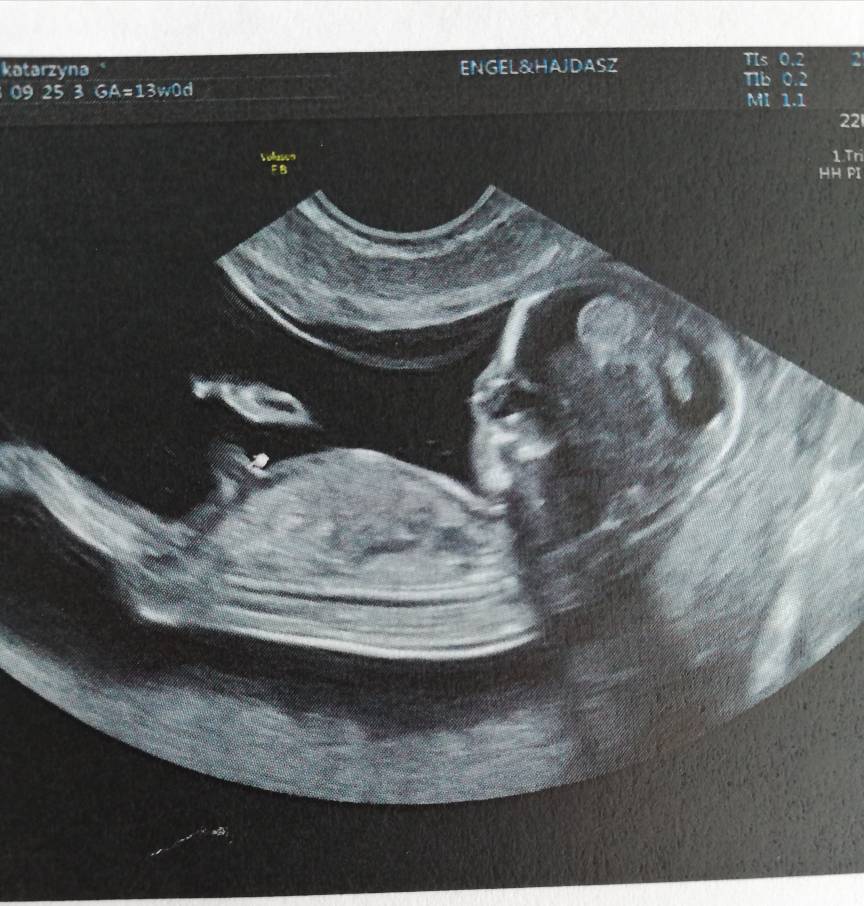

Cudne zdjęciaJa wczoraj byłam na prenatalnych ale po wizycie żeby uczcić poszłam na zakupy a wieoeczorem szybko padlam więc dzisiaj pisze dopieroDzidziuś ma już 6,61 cm tydzień ciąży identyczny jak z usg 13+0. Termin na 02.04. Wszystkie wymiary idealne, pięknie fikal dzidziuś

Wstępnie dr obstawia dziewczynkę ale jeszcze mamy się nie nastawiac. Trochę szok dla mnie bo byłam pewna że będzie drugi chłopczyk. Zobacz załącznik 901859Zobacz załącznik 901860Zobacz załącznik 901861Zobacz załącznik 901863